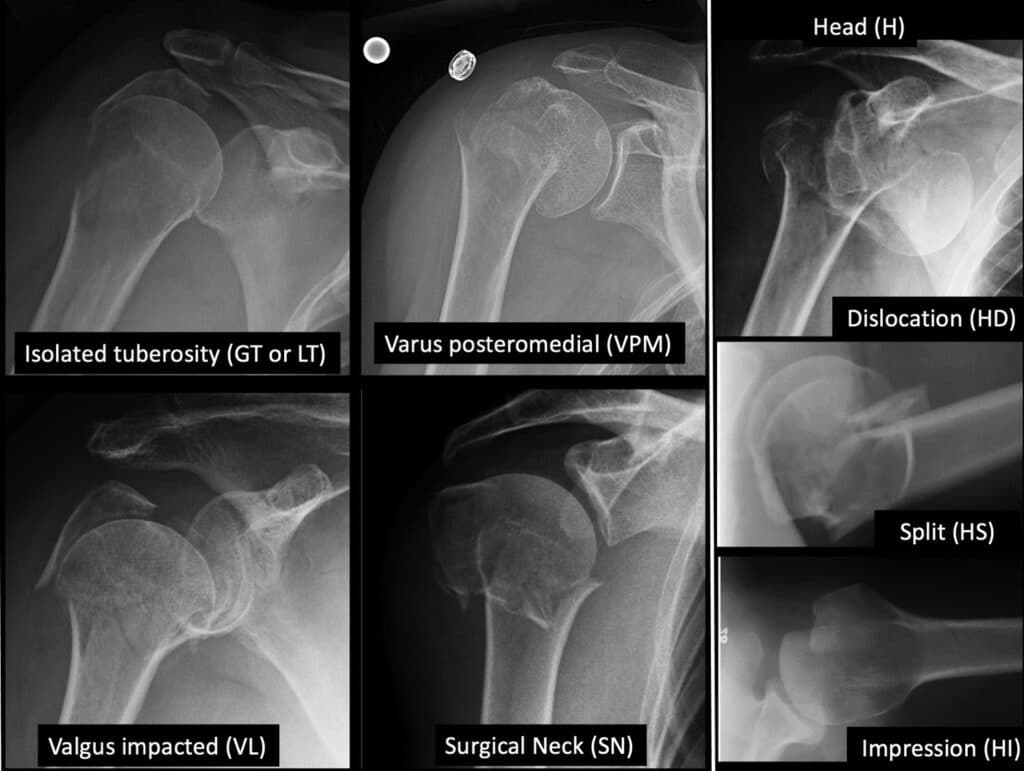

Proximal humerus fractures are classified based on the Mayo-FJD classification, which describes 7 common fracture patterns that each have different outcomes when treated without surgery.

Fractures of the Greater Tuberosity or Lesser Tuberosity

Fractures of the Greater Tuberosity (GT) or Lesser Tuberosity (LT) may occur with or without shoulder dislocation. Nonoperative treatment risks impingement or rotator cuff dysfunction, particularly if displaced.

Fractures with Severe Head Compromise

Fractures involving severe head compromise, such as head dislocation (HD), head splitting (HS), or head impaction (HI), may lead to persistent instability, maltracking, and osteoarthritis. Surgery is usually recommended due to these anticipated complications.

Varus Posteromedial Fractures

Varus posteromedial (VPM) fractures involve comminution and collapse at the posteromedial neck-head junction, potentially resulting in malunion if untreated. Nonunion is rare due to bony impaction, and adverse outcomes include decreased range of motion and loss of function.

Valgus Fractures

Valgus (VL) fractures displace the humeral head in a valgus direction, and the greater tuberosity is almost always fractured (VL-GT). Malunion is a potential adverse outcome, with added instability if the medial periosteal hinge is disrupted. Avascular necrosis may occur with nonsurgical treatment.

Surgical Neck Fractures

Surgical neck (SN) fractures occur at the metaphyso-diaphyseal junction, separating the head and tuberosities from the diaphysis. Lack of impaction distinguishes SN fractures from VPM and VL fractures. Nonoperative treatment risks nonunion, especially with substantial displacement or compromised healing potential.